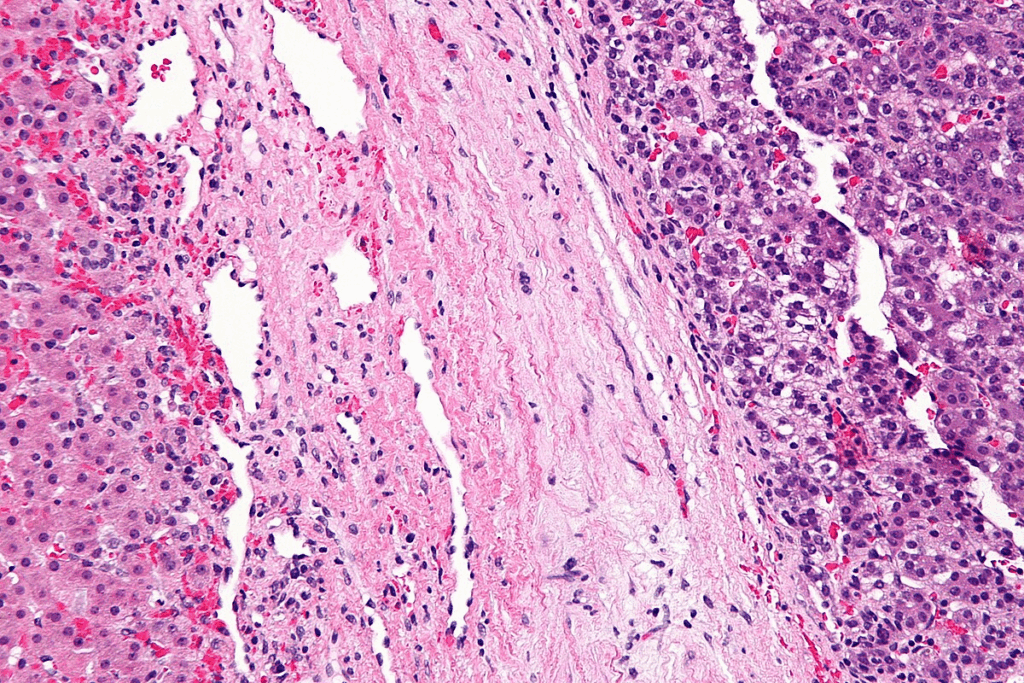

Hepatoblastoma is a cancer of the liver that mostly happens in kids under 3. It starts from immature liver cells. There are different types of hepatoblastoma, each with its own characteristics.

These types include fetal, embryonal, macrotrabecular, and small cell undifferentiated. Knowing the type helps doctors predict how well a child will do and plan treatment.